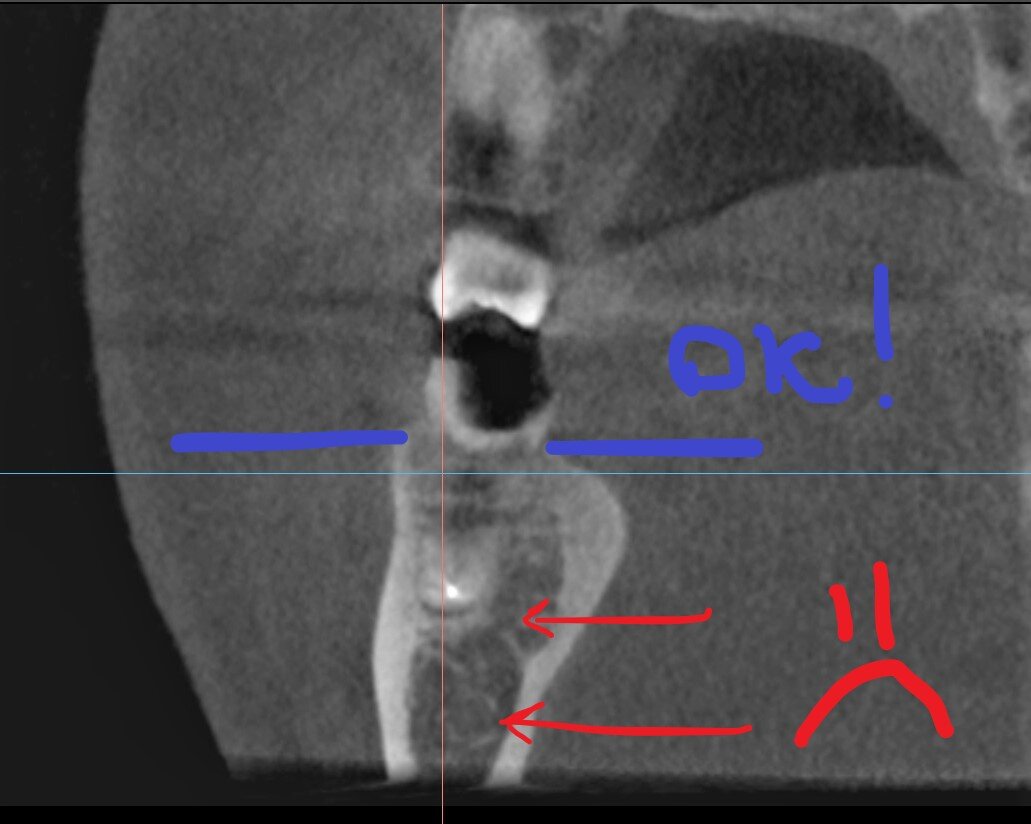

2. Пористая, мягкая кость.

Зуб под удаление. Но одномоментная имплантация в этом случае рискованна.

Пористая кость из-за своих физических свойств плохо "держит" имплантат, высок риск отторжения. Имплантолог при работе с ней использует специальные методики и свёрла - кость не "выпиливается", а костная стружка остаётся в лунке, прижимается к краям, уплотняет стенки дефекта.

Уровень - отличный. А вот структура кости подкачала.